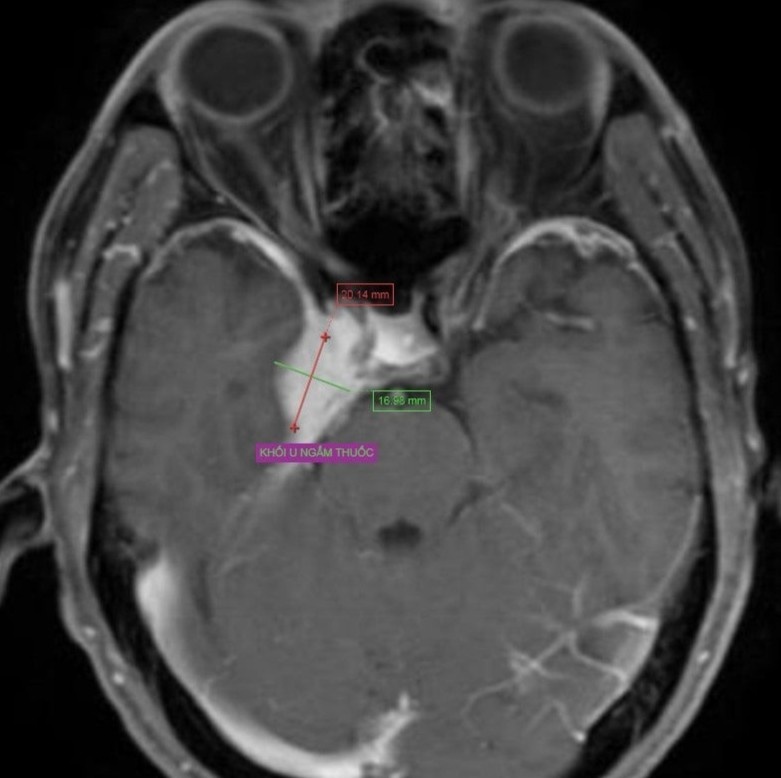

Kết quả chụp cộng hưởng từ của bệnh nhân phát hiện khối u màng não. Ảnh: BVCC.

Tại bệnh viện, qua quá trình thăm khám lâm sàng, bác sĩ chỉ định bệnh nhân chụp cộng hưởng từ (MRI) sọ não. Kết quả cho thấy có hình ảnh khối u màng não kích thước khoảng 2x3 cm.